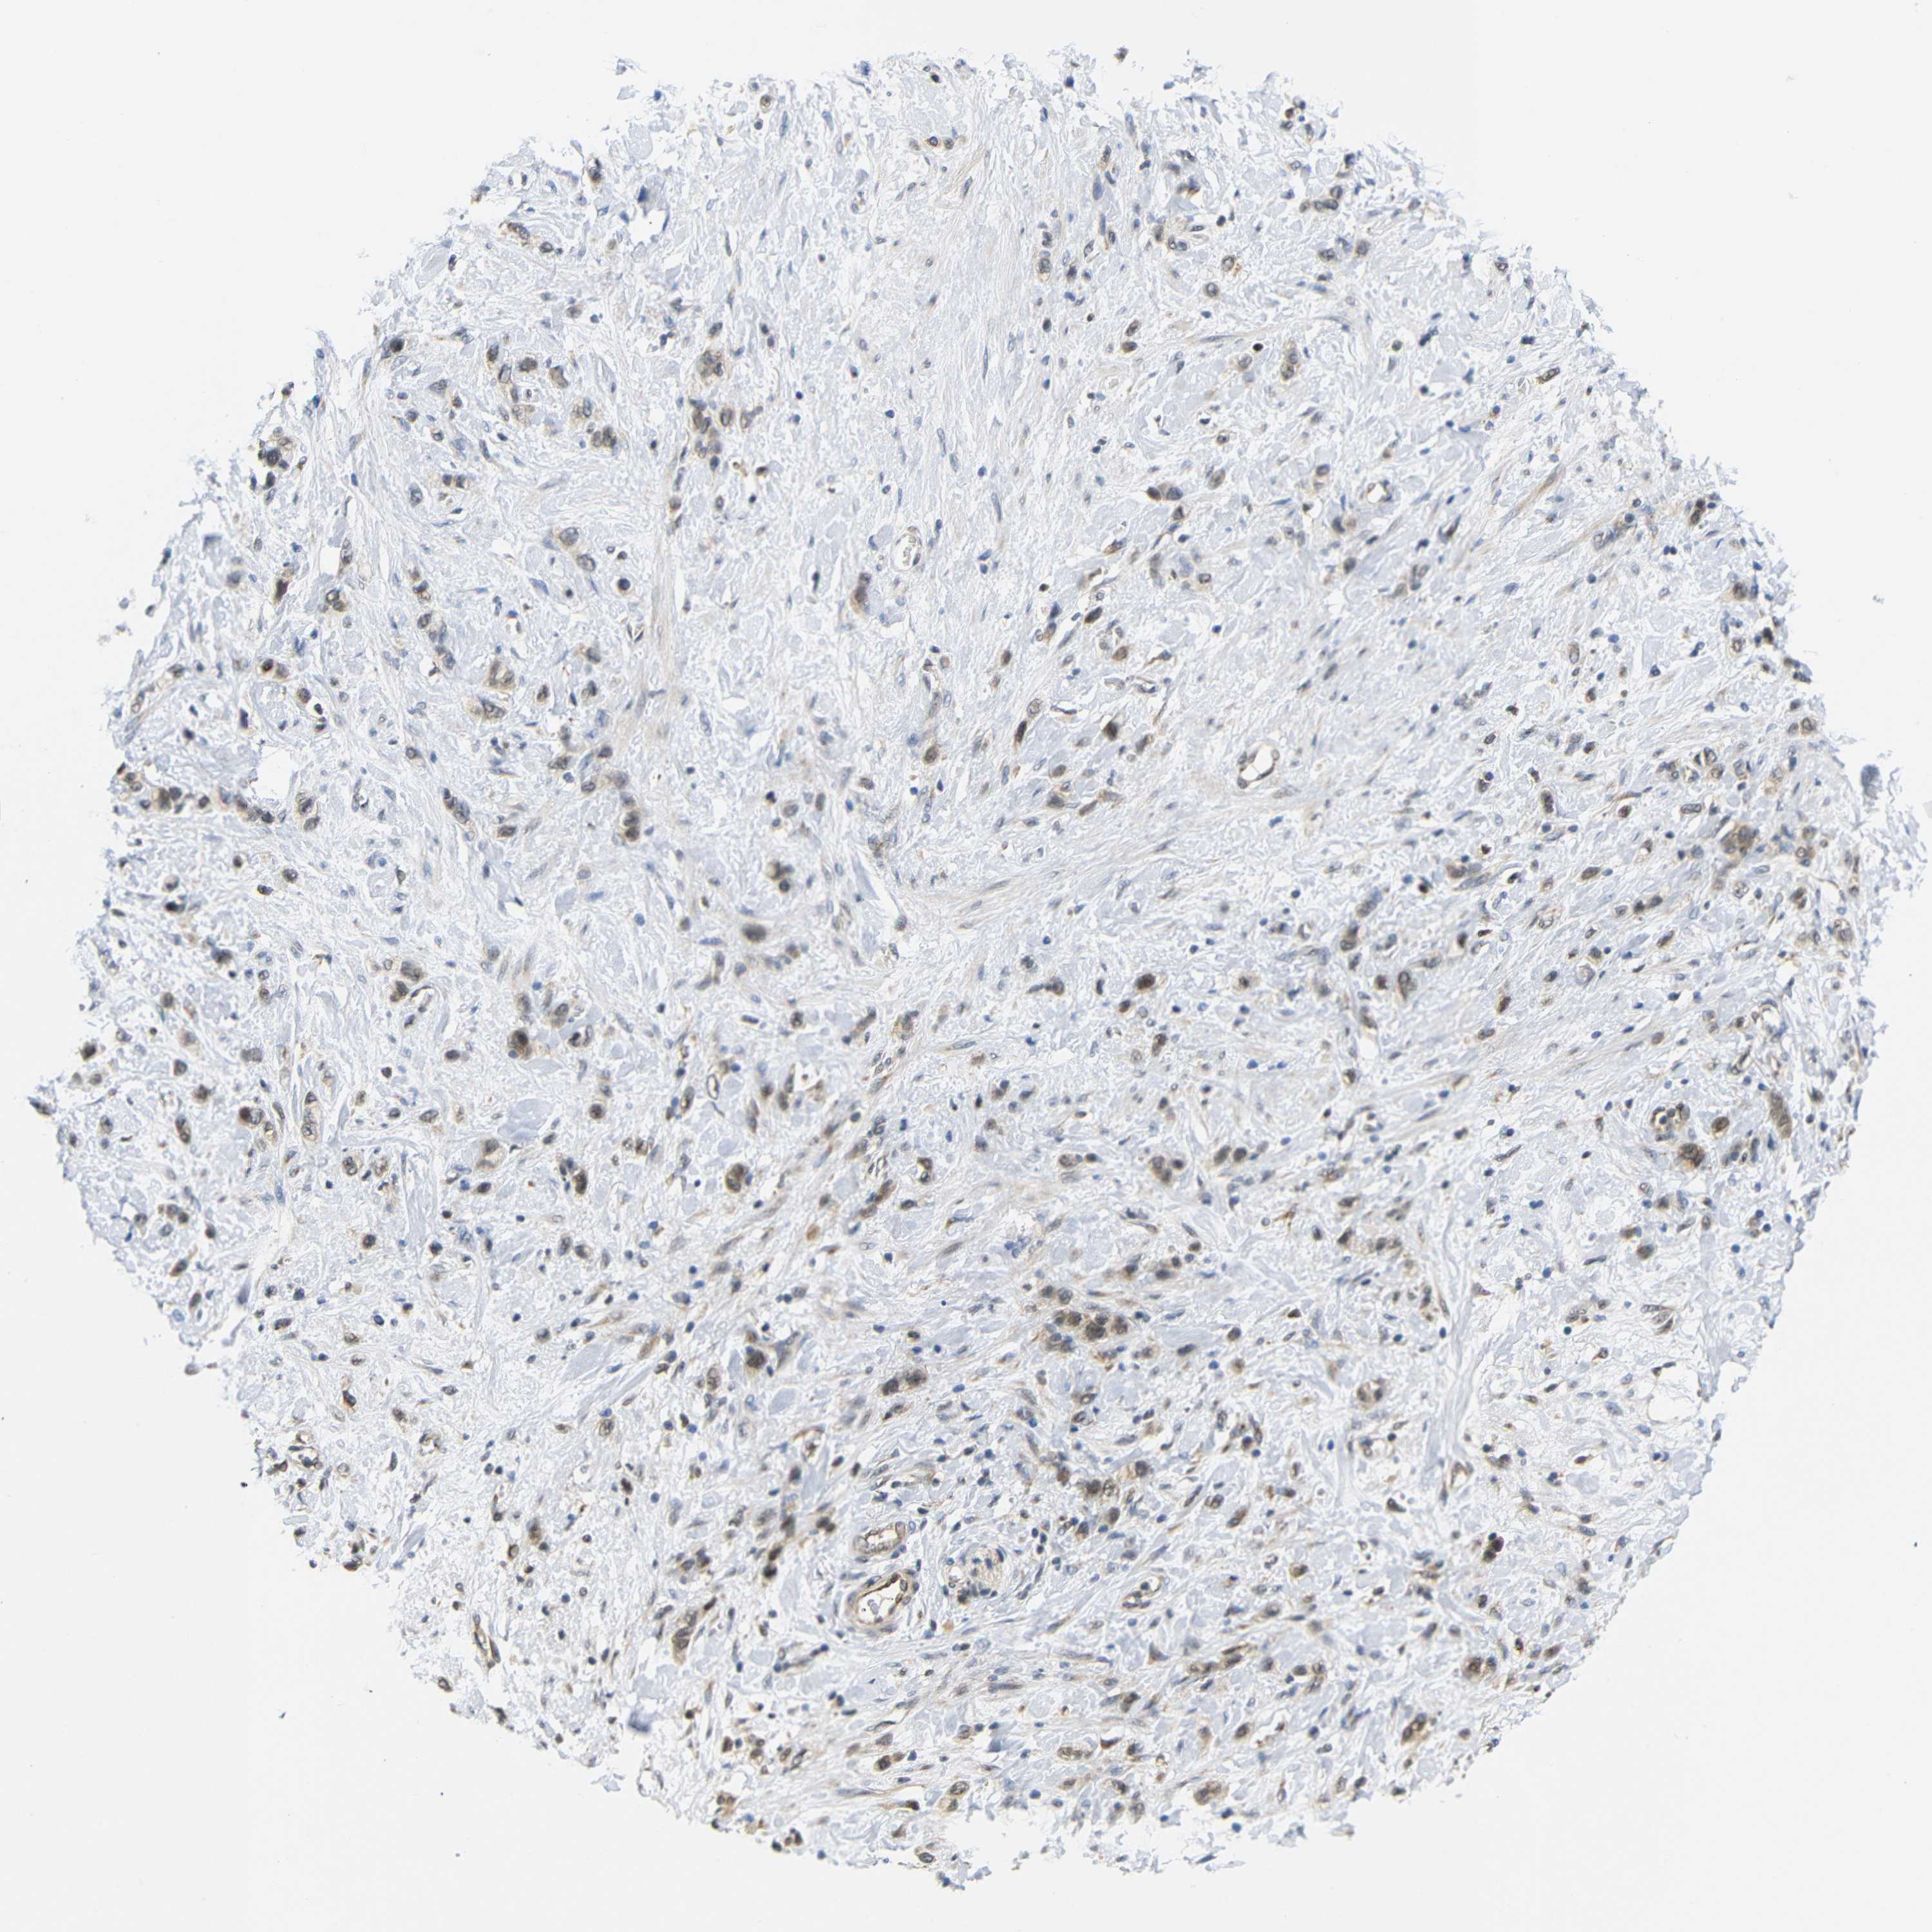

STOMACH CANCER - Protein expressioni

A mouse-over function shows sample information and annotation data. Click on an image to view it in a full screen mode. Samples can be filtered based on level of antibody staining by selecting one or several of the following categories: high, medium, low and not detected. The assay and annotation is described here.

Antibody stainingi

Antibody staining in the annotated cell types in the current human tissue is reported as not detected, low, medium, or high, based on conventional immunohistochemistry profiling in selected tissues. This score is based on the combination of the staining intensity and fraction of stained cells.

Each image is clickable and will lead to virtual microscopy that enables deeper exploration of all samples and also displays staining intensity scores, fraction scores and subcellular localization as well as patient and tissue information for each sample.

Antibody HPA071370

Antibody CAB013080

Staining

High

Medium

Low

Not detected

Intensity

Strong

Moderate

Weak

Negative

Quantity

>75%

75%-25%

<25%

None

Location

Nuclear

Cytoplasmic/membranous

Cytoplasmic/membranous,nuclear

Adenocarcinoma, NOS

Adenocarcinoma, High grade